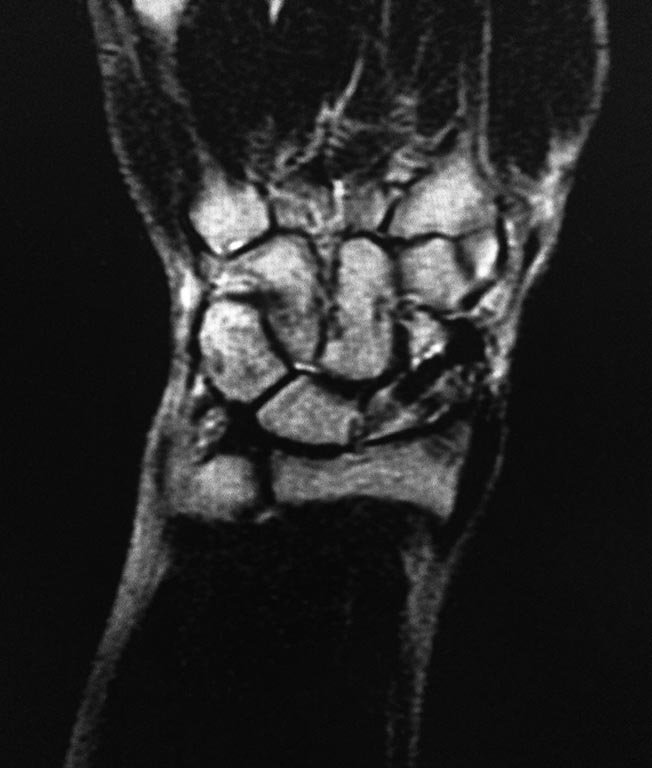

Трехгранная кость ?

Здравствуйте. Мужчина 30 лет. Травма около 5ти лет назад

МОС винтом, в данное время в проекции ладьевидной кости болей нет, осевая нагрузка на 1ю пястную кость безболезненная, боли беспокоят при пальпации в проекции трехгранной кости и движениях в лучезапястном суставе(при пассивных и активных движениях возникают острые боли, так же в проекции трехгранной кости). На МРТ отмечаются проблемы в этой зоне. Со слов пациента, при периодических болях принимает таблетку найза, после чего все проходит.